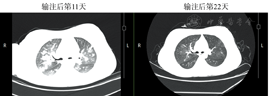

患者,女,12岁,2016年11月17日在外院诊断为B-ALL,当时融合基因筛查示E2A-PBX阳性,染色体核型分析示der(19),t(1;19)(q23; p13)。给予PVLD方案诱导治疗后取得完全缓解,之后予以CAM、PVLD及大剂量甲氨蝶呤(MTX)等方案化疗4个疗程。2017年6月5日患者疾病复发,2017年8月1日转至我科行CAR-T细胞治疗。2017年8月5日在患者父母签署知情同意书后,采取患者外周血60 ml用于制备CAR-T细胞,在等待CAR-T细胞回输期间,患者出现反复高热、齿龈疼痛及全身骨痛,外周血幼稚细胞增多,考虑疾病进展,给予VMP(长春地辛+米托蒽醌+甲泼尼龙)方案化疗控制肿瘤负荷,患者于9月18日出现2次癫痫发作(部分性发作),脑脊液常规生化检查及影像学检查未发现异常,予以卡马西平口服预防治疗。9月20日复查骨髓示原始淋巴细胞占0.940,血常规示HGB 71 g/L, PLT 16×109/L, WBC 6.4×109/L,中性粒细胞2.8×109/L,淋巴细胞0.8×109/L,幼稚细胞占0.38。血清细胞因子检测示IL-6 11.8 pg/ml(正常参考值<5.9 pg/ml),IL-2受体1 119 U/ml(正常参考值223~710 U/ml),TNF-α 6.3 pg/ml(正常参考值<8.1 pg/ml)。9月21日起予以FA(氟达拉滨25 mg/m2+阿糖胞苷1 g/m2)方案预处理化疗3 d,9月27日(第0天)起行患者自体CAR-T细胞输注,输注CAR-T细胞总量为0.3×106/kg,分2 d输注(第0天输注CAR-T细胞总量的30%,第1天输注细胞总量的70%)。患者于10月4日(第7天)开始出现发热且体温逐渐增高,血清细胞因子检测示IL-6 13.6 pg/ml,IL-2受体1 415 U/ml,TNF-α 11 pg/ml。10月5日(第8天)患者呈持续高热,体温最高达41.3 ℃,给予对乙酰氨基酚口服及物理降温等措施均退热效果不佳,予以托珠单抗(8 mg/kg)静脉滴注治疗后体温在2 h后明显下降,一度恢复至正常,次日起患者又出现发热,体温逐渐升高,10月7日(第10天)体温最高达39.9 ℃。10月8日(第11天)起患者出现胸闷、气急等不适,伴阵发性呛咳,指末氧饱和度下降至85%~92%,胸部CT示两肺多发渗出性改变(图1);血气分析提示低氧血症,血常规示HGB 67 g/L,PLT 17×109/L,WBC 1.18×109/L,中性粒细胞0.2×109/L,幼稚细胞占0.02;生化检查示总胆红素(TBIL)17.5 μmol/L(正常参考值5.1~20.5 µmol/L),ALT 199 U/L(正常参考值7~40 U/L),AST 949 U/L(正常参考值13~35 U/L),LDH 17 060 U/L(正常参考值120~250 U/L),尿酸539 μmol/L(正常参考值155~357 μmol/L);血清细胞因子检测示IL-6>1 000 pg/ml,IL-2受体2 985 U/ml。予以面罩吸氧(5 L/min),积极抗感染、保肝,水化、碱化和利尿治疗,并第二次使用托珠单抗(8 mg/kg)治疗。10月9日(第12天)患者体温恢复正常,但胸闷、气急症状无缓解,出现皮肤多处大片瘀斑,出凝血常规示凝血酶时间(TT)54.5 s(正常参考值14~21 s),APTT 37.5 s(正常参考值25.0~36.2 s),纤维蛋白原1.82 g/L(正常参考值2.00~4.50 g/L),D-二聚体37.03 mg/L(正常参考值<0.55 mg/L),纤维蛋白降解产物(FDP)112.2 g/L(正常参考值2.0~4.5 g/L);生化检查示TBIL 48.6 µmol/L,ALT 250 U/L,AST 1 102 U/L,LDH 18 561 U/L。患者肝功能损害及凝血功能障碍加重,加强保肝和输注血浆、血小板等支持治疗;予以甲泼尼龙(40 mg每12 h 1次)静脉滴注,BiPAP呼吸机辅助通气。之后患者皮肤出血倾向改善,胸闷气急症状好转,氧需求量逐渐减少。10月12日(第15天)复查血常规示外周血幼稚细胞消失,出凝血常规示APTT 20 s,TT 30.2 s,D-二聚体11. 31 mg/L,FDP 53.2 g/L,肝功能检查示TBIL 35.1 µmol/L,ALT 117 U/L,AST 329 U/L,均较前好转,停止BiPAP呼吸机使用。10月14日(第17天)下午起患者突然出现四肢抽搐伴双眼凝视,每次持续5~10 min,之后反复发作,发作间期意识不清,考虑为癫痫持续状态。脑电图显示背景活动见α节律,间有θ波及少量低波幅β波,双侧额颞顶部偶见尖慢波发放,支持大脑皮层的广泛损害表现。予以地西泮(微泵静注5 mg/h)抗癫痫,甘露醇脱水,激素改为地塞米松(10 mg每6 h 1次)静脉滴注治疗,2 d后患者意识恢复正常,无癫痫发作,予以口服丙戊酸钠维持治疗,此时检查头部MRI可见两侧大脑皮层散在片状异常信号影(图2);激素逐渐减量至10月19日(第22天)停用。10月25日(第28天)血常规示HGB 95 g/L,PLT 13×109/L,WBC 1.06×109/L,中性粒细胞0.2×109/L,无幼稚细胞;C反应蛋白(CRP)0.1 mg/L;肝肾功能、出凝血常规及D-二聚体、FDP均正常;血清细胞因子IL-6 199 pg/ml,IL-2受体1 463 U/ml,TNF-α 19.1 pg/ml。10月30日(第33天)好转出院。